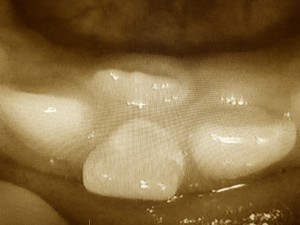

今回は乳歯がかなり揺れており、上の前歯と変な当たり方をして気になることと、永久歯の出てきた位置を考え早期に抜いたほうが良いとお伝えし、抜歯を行いました。

抜歯後は永久歯が生えるスペースになり、自然に永久歯が外側に出てくることもありますし、スペースが小さくて入らないなんてこともよくあります。そのような場合には、側方に歯のアーチ、顎骨を広げるような矯正治療を必要とする場合もあります。